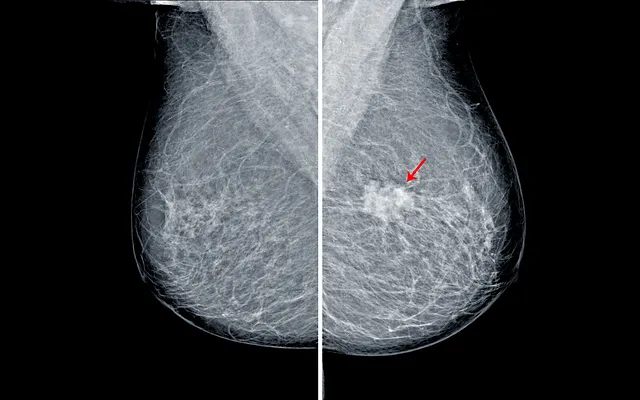

I have heard there is a new technique called 3D mammography or Tomosynthesis. Food and Drug Administration FDA has issued a safety alert for patients who had mammograms at the Allison Breast Center at Monument Radiology located in Richmond VA on or after June 17 2018 due to possible problems with the quality of their mammograms. Food and Drug Administration FDA has revoked its Mammography Quality Standards Act MQSA certificate for Allison Breast Center at Monument Radiology in Richmond VA.

Allison Breast Center Monument Radiology Safety Alert Background Information. -- The Virginia Board of Medicine called Dr. The Allison Breast Center said it is now checking messages and emails on Tuesdays and Wednesdays.

Mammography Problems At Allison Breast Center At Monument Radiology In Richmond

Fda Allison Breast Center Did Not Meet The Standards For Mammography Quality